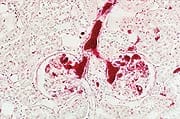

The link between cancer and genetic mutation has become much clearer in the past several years, with the discovery of tumor suppressor genes and proto-oncogenes. Tumor suppressor genes keep cell division within normal bounds, while proto-oncogenes drive the process of cell division forward. Mutations to either type of genes can result in cancer—the uncontrolled growth of cells.4,5 The list of diseases attributable to somatic mutation is growing rapidly.1 This is why it is so vitally important to block gene and DNA mutations during our lifetime using targeted antimutagenic agents. Among the most powerful mutation-blocking agents is chlorophyllin.6,7 Chlorophyllin is a semi-synthetic, water-soluble form of the plant pigment chlorophyll. Unlike some herbal ingredients that indicate cancer protection at high doses (hundreds of milligrams per kilogram of body weight in animal or human studies), chlorophyllin possesses anti-cancer and DNA damage-protection effects at much lower amounts. In fact, 40-100 mg of chlorophyllin three times daily is all many humans need to duplicate studies showing excellent protection against a wide range of dietary compounds that are known to cause cancer in humans and animals.8,9 Here, we’ll explore the latest research on chlorophyllin’s numerous health-promoting effects—from prevention of cancers caused by diet to managing a serious disease called leukopenia.8,9 Neutralizing Dietary Carcinogens and Preventing Multiple CancersAs Life Extension Magazine® first pointed out over a decade ago, the integrity of human DNA is under constant assault owing to the way we cook our food. Well-done meats—grilled, fried, or barbecued beef, pork, and chicken with skin—contain varying quantities of the powerful carcinogens benzopyrene and PhIP (2-amino-1-methyl-6-phenylimidazo [4,5-b] pyridine).8,10-12 Baking or stewing meat at moderate temperatures has not been shown to produce cancer-causing chemicals. These cancer-causing agents are ubiquitous. Benzopyrene is so commonplace and poses such a threat to human health that some countries test all imported foods for benzopyrene content. In sufficient quantities, this potent carcinogen binds to DNA, causing severe genetic mutation in affected cells. Once these cells divide, they can become precancerous—or cancerous.13 Chlorophyllin appears to counter benzopyrene’s carcinogenic effect in four distinct ways:

Among the 180 people who took 100 mg of chlorophyllin three times daily in the Johns Hopkins study, urinary levels of DNA-aflatoxin adducts went down 55% compared to untreated people.8 The formation of DNA adducts often leads to DNA mutations and the formation of a cancer cell. A drop in DNA mutation rates such as would be expected from the participants in this study could delay the onset of cancer by as much as twenty years.23 Colon CancerThe most abundant carcinogen in fried meats, PhIP is a heterocyclic amine compound.24 These form when amino acids (the building blocks of proteins) and creatine (a chemical found in the muscle tissue) react at high temperatures. When PhIP is administered to laboratory animals, it speeds the development of aberrant crypt foci, the structural precursors of colon cancer. Mounting scientific research clearly indicates that chlorophyllin can help protect the colon against this lethal carcinogen. In a recent study, it cut the number of pre-cancerous aberrant crypt foci by 50% and accelerated the elimination of unmetabolized PhIP.12 In 2008, chlorophyllin was shown to inhibit the mutagenic effect of another heterocylic amine found in cooked meat and other foods called IQ (2-hydroxyamino-3-methylimidazo [4,5-f] quinoline). Researchers found that chlorophyllin rapidly degraded IQ’s mutagenic metabolite, potentially interrupting the development of colon cancer at an early stage.25 In another study, mice were given dimethylhydrazine, a carcinogen shown to specifically induce tumors in the colon. When chlorophyllin was administered concurrently, it prevented the formation of tumors by inhibiting the protein complexes that enable mutant DNA to replicate.26 Breast Cancer